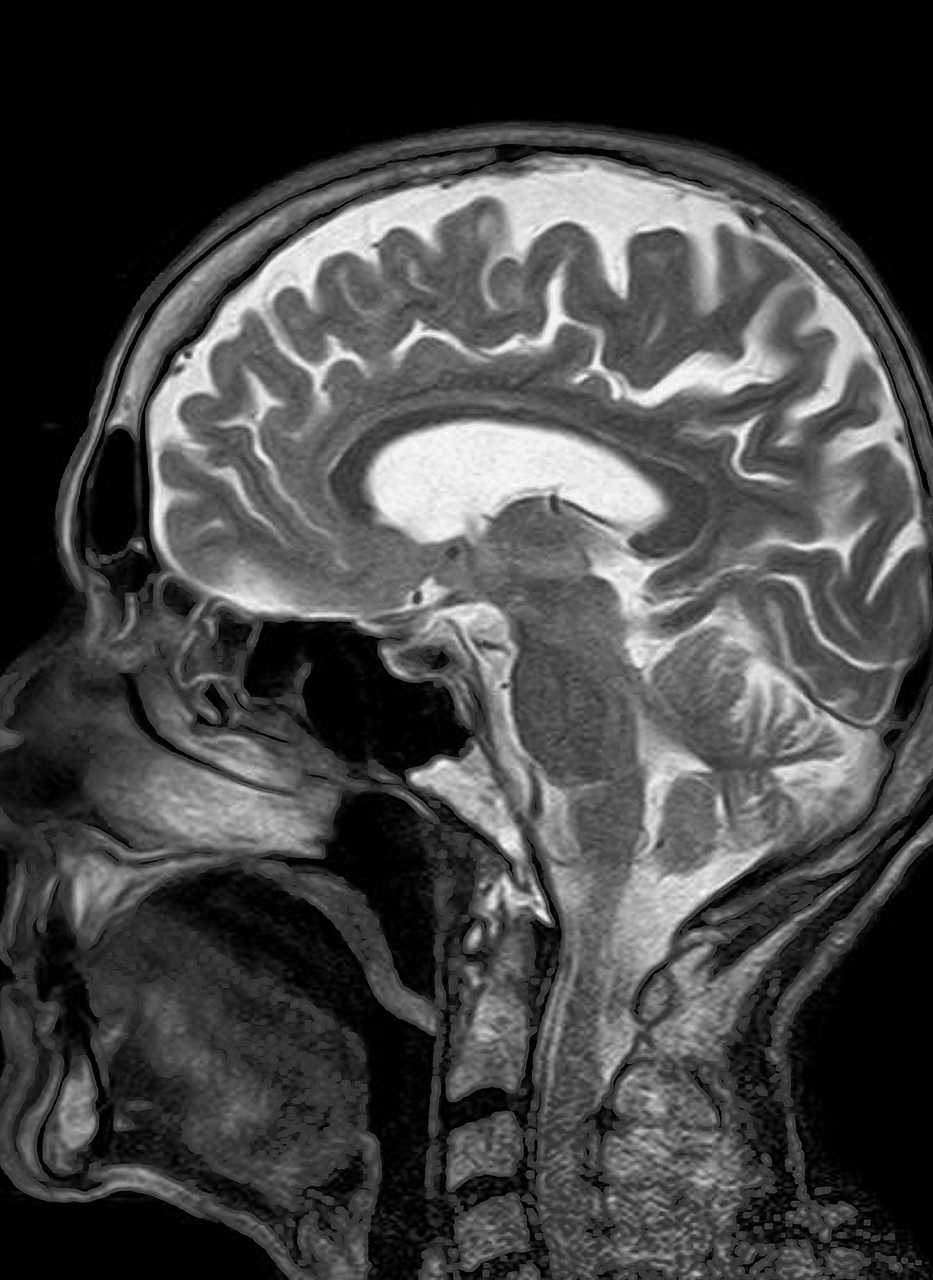

• New technologies such as CT and MRI scanning are data demanding and would be impossible without technology of today